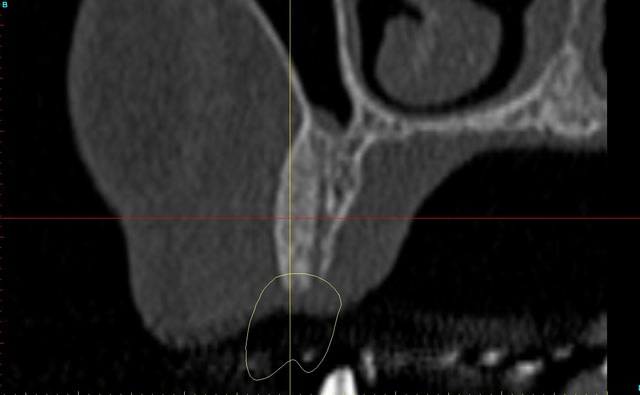

Dar axial lebnbu - Eugenol

Dar axiali qui1is - Eugenol

Dar11 cyo3el - Eugenol

Dar13 alznrp - Eugenol

Dar13i aujibg - Eugenol

Dar14 actm24 - Eugenol

Dar15 zvi82y - Eugenol

Dar23i g6nxds - Eugenol

Dar24 vzfroa - Eugenol

Dar25 lcptyk - Eugenol

Dar 3d xkb3uv - Eugenol

Dar  3di ngfcc4 - Eugenol

Dar  3dl fwmdk6 - Eugenol

Céramik

image 8, il semble y avoir une zone entre le greffon et l'os ?

C'est intégré ?